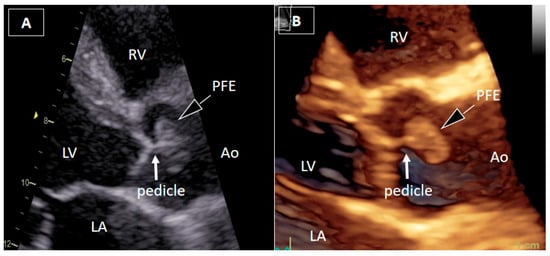

Papillary Fibroelastoma of the Aortic Root Causing Intermittent Coronary Ostial Obstruction: The Diagnostic Power of 3D Transesophageal Echocardiography

Bečić, T.; Perković-Avelini, R.; Fabijanić, D. Papillary Fibroelastoma of the Aortic Root Causing Intermittent Coronary Ostial Obstruction: The Diagnostic Power of 3D Transesophageal Echocardiography. Diagnostics 2026, 16, 168. https://doi.org/10.3390/diagnostics16010168